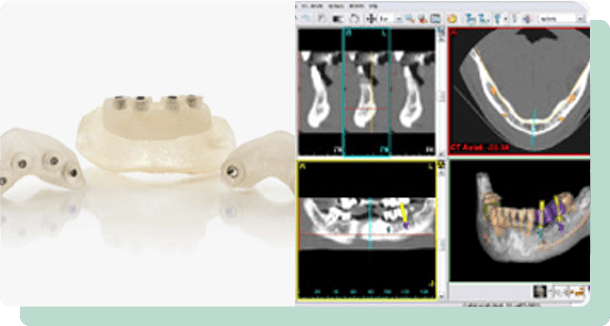

まずは、CTなどでしっかり診査・診断をして、患者さまに最適な治療プランを提案。CT撮影された画像をコンピューター上で立体化する3Dシミュレーションシステムを使って、より正確に顎の状態を診断し、さらに、インプラント手術のシミュレーションを行って、適切な埋め込み位置を決定していきます。

3Dシミュレーションシステム

(Simplant)で正確に判断。

CT撮影された画像をコンピューター上で立体化する3Dシミュレーションシステム。(シンプラント Simplant)

この装置を使って、より正確に顎の状態を診断し、さらに、インプラント手術のシミュレーションを行って、適切な埋め込み位置を決定していきます。